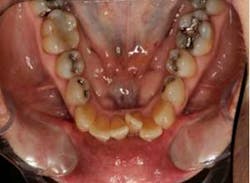

SFOT was used with a high-tech clear aligner to address hard- and soft-tissue deficiencies and severe maxillary and mandibular arch constriction.

A healthy, 57-year-old female presented with a lifelong desire for healthy, straight teeth and a beautiful smile. She had been told numerous times that it was not possible without premolar extractions.